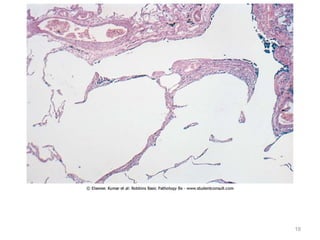

Morphology

• In the acute phase of ARDS, the lungs are dark

red, firm, airless, and heavy.

• Microscopic examination reveals capillary

congestion, necrosis of alveolar epithelial cells,

interstitial and intraalveolar edema and

hemorrhage, and (particularly with sepsis)

• Lungs are heavy, firm, red & boggy

• Congestion, interstitial & intra-alveolar edema,

inflammation & fibrin deposition

• The alveolar walls become lined with waxy hyaline

membranes

• Resolution is unusual, more commonly intra-

alveolar fibrosis

• Thickened alveolar septa caused by proliferation of

interstitial cells